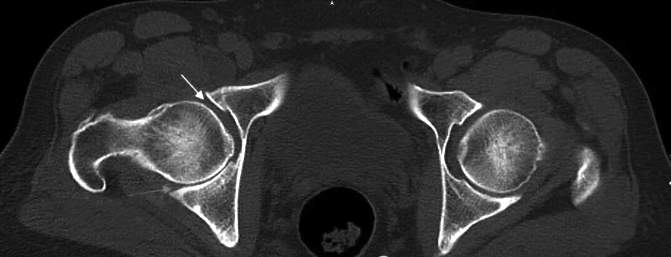

股骨头坏死发展到一定阶段,会出现“裂缝”(软骨下骨折)、“空洞”(囊性变)等。其实,股骨头内有“空洞”,不一定意味着坏死。下面,我举例说明。 病例 这是一位男性患者,今年67岁,6个月前无明显诱因出现右髋部大腿内侧及右膝关节疼痛,劳累后疼痛加重。他到当地医院拍片。当地医院医生看了一下片子,认为是右侧股骨头坏死,遂让患者口服药物治疗。口服药物治疗1个月,患者的疼痛未见明显减轻,遂来到河南省洛阳正骨医院就诊。 我看了他的MRI(磁共振成像)片,发现和股骨头坏死的影像非常相似,但的的确确是骨性关节炎。 仔细看MRI片(图1),可见左侧股骨头(L)很圆,右侧股骨头不仅不圆且髋臼有内陷。将MRI片与CT片(图2)结合起来,可以明确诊断。CT片可见关节面下囊性变,关节间隙不等宽,周围还有骨质增生。 成人发育不良被确诊的年龄范围很大,早期可以在青春期剧烈运动后发现,也可以在40岁~50岁偶尔有疼痛时发现,当然多在60岁~70岁时被确诊——确诊时间取决于具体的头臼匹配、体重、工作性质、运动或劳动量。 当然,还可以换个思路来理解疼痛的机制——关节不稳定造成磨损增加,盂唇受到撞击后发生撕裂。 一般认为,50岁以下的髋关节发育不良可以考虑髋臼周围截骨术;50岁以上,对于疼痛无法通过保守治疗获得长期满意效果,首选关节置换治疗。 术中可见股骨头负重区软骨已经磨损殆尽,由此引起的疼痛是无法通过保守治疗解决的。 为什么骨性关节炎和股骨头坏死易混淆 骨性关节炎是一种以关节软骨退行性变和继发性骨质增生为特征的慢性关节疾病,多见于中老年人,女性发病率略高于男性。其核心病理改变是关节软骨的变性、破坏,导致关节疼痛、僵硬、肿胀及活动受限。 骨性关节炎与股骨头坏死在症状、影像学表现上存在诸多相似之处,这导致两者在临床诊断中容易混淆。 症状相似性 1.疼痛特点重叠 两者均可表现为髋部疼痛,且活动后加重。 骨性关节炎的疼痛多为渐进性,休息后可缓解。股骨头坏死引发的疼痛可能夜间明显,且休息后无法完全缓解。 2.关节功能影响 骨性关节炎和股骨头坏死均会导致活动受限、跛行等症状,且体格检查(如“4”字试验阳性)结果相似。 影像学表现交叉 1.早期影像学差异不明显 骨性关节炎的典型表现为关节间隙狭窄、骨赘形成。而股骨头坏死早期X线检查结果可能正常,需通过MRI检查发现骨髓水肿或“新月征”。 若仅做X线检查,可能漏诊早期股骨头坏死。 2.晚期病变相互关联 股骨头坏死晚期可因股骨头塌陷继发髋关节骨性关节炎。此时影像学表现可能同时具备两者特征,增加鉴别难度。 如何避免误诊 结合多种检查手段:X线联合MRI检查可提高诊断准确性。 关注疼痛细节:若有夜间痛、静息痛,更倾向于股骨头坏死。 详细询问病史:明确激素使用、饮酒史等关键信息。 (作者供职于河南省洛阳正骨医院)